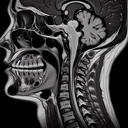

МРТ, КТ, УЗД — розповідає лікар

МРТ грудного відділу хребта

МРТ грудного відділу хребта – це неінвазивний метод діагностики, що використовує магнітні поля та радіохвилі для отримання детальних зображень цієї частини тіла. Він допомагає виявити різні патології, такі як грижі міжхребцевих дисків, дегенеративні зміни, пухлини, інфекції чи травми. Процедура є безпечною і безболісною, не використовує іонізуюче випромінювання, що робить її безпечною для різних категорій пацієнтів, включаючи дітей і вагітних (за показаннями)...